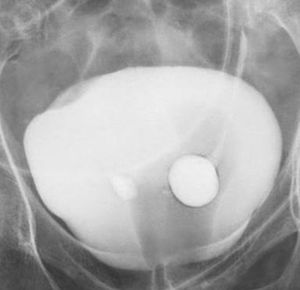

This is uretrocele in which ivp finding show cobra head sign.....see Dr. imtiyaz Ans.

Uretrocele✌️You are correct. And that surgery is called Ureteric meatotomy